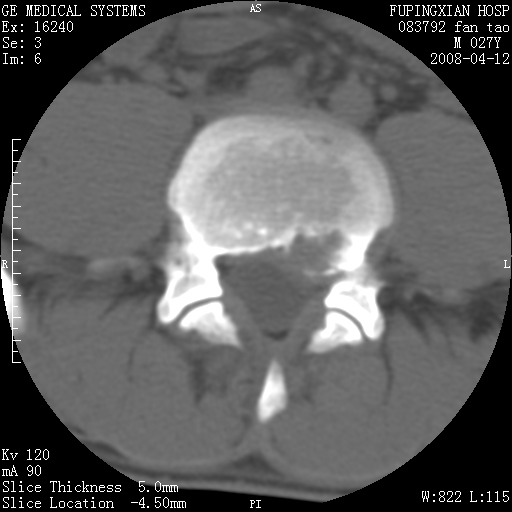

以下是引用前行在2008-4-13 13:53:00的发言:[br]椎间盘髓核终板下突出形成许莫氏结节及椎间盘突出,建议mr检查

以下是引用xclzq_910在2008-4-13 12:43:00的发言:[br]这个应该没什么了,椎间盘突出后反应性骨质吸收硬化.建议mr